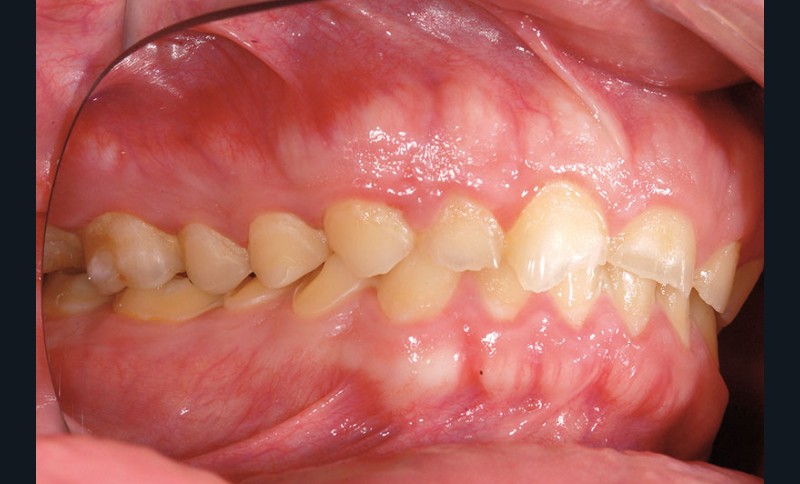

À l’examen clinique, les dents, principalement antérieures, présentent des pertes de substances importantes de classe V selon la classification ACE (Anterior Clinical Erosive Classification) de Vailati [1] (fig. 1 à 6).

Le parodonte marginal est de type 1 selon la classification de Maynard et Wilson [2]. On note également la présence d’une grande quantité de gencive attachée située apicalement par rapport aux lésions dentaires.